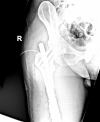

Krček minus - petrochantericka zlomenina

Prý jsem ještě mladý tak mělo smysl operovat a dávat výztuž, ale ještě neví jestli napořád nebo budou vyndavat.

Jinak jsem prý měl štěstí, že to není klasická zlomenina krčku, ale jak to bylo v rychlosti tak jsem si odlomil krček od stehenní kosti, prý dynamická zlomenina sportovců.

Pedro404 – ne, je to o operaci, mám jen 3 malé otvory kudy dávali šrouby, tj 6 stehů

Tož vitaj :-) Petrochanterická zlomenina, mám gama hřeb se čtyřmi vruty od června 2009, pohoda, nechali mi ho tam nafurt, ani o tom nevím. Velká rychlost do zatáčky a trochu písku a bylo to :-)